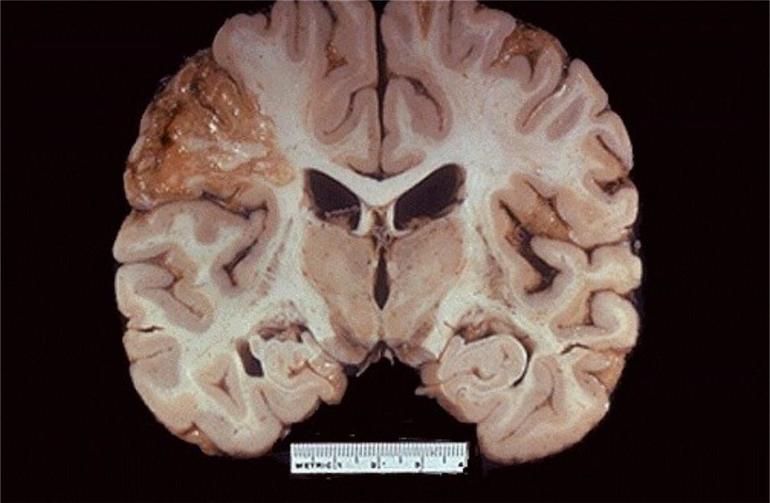

Атеросклероз сосудов

Это довольно серьезное заболевание, которое на ранних стадиях легко поддается диагностике и возникает из-за нарушений в кровообращении. Из-за накопления холестерина на стенках сосудов их просвет сужается, а эластичность снижается. Заболевание проявляется продолжительными головными болями и ухудшением памяти. Бляшки представляют опасность тем, что могут отклеиваться от стенок сосудов и перемещаться по кровотоку, что приводит к закупорке других сосудов. Это, в свою очередь, может спровоцировать образование тромбов.

- Тромбоз: при запущенных формах заболевания холестериновые отложения увеличиваются, распадаются на мелкие фрагменты, что приводит к образованию сгустков, которые блокируют мелкие артерии. В результате сосуды закупориваются, и в некоторых случаях это может закончиться летальным исходом.

- Инфаркт мозга: полная блокировка сосуда вызывает кислородное голодание клеток мозга, что приводит к ишемическому инсульту. Состояние пациента становится критическим: наблюдаются паралич конечностей, онемение языка и утрата речи. Без своевременной медицинской помощи возможен фатальный исход.

- Кровоизлияние в мозг: при высоком артериальном давлении может произойти разрыв узкого сосуда, что приводит к попаданию крови в мозговые ткани и воспалению. В большинстве случаев это заканчивается смертью.